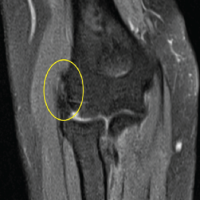

A 37-year-old male with a history of right anterior cruciate ligament (ACL) reconstruction presented with severe loss of knee motion secondary to arthrofibrosis and a large cyclops lesion measuring over 3 cm anterior to the graft. Additional imaging findings included a full-thickness cartilage lesion of the medial femoral condyle and diffuse scar tissue in the suprapatellar pouch and posteromedial capsule. The patient underwent arthroscopic excision of the cyclops lesion, extensive anterior and posterior capsular releases, and a reverse notchplasty. A posteromedial portal was used to access the scarred posterior compartment. To help regain knee extension, the ACL graft was intentionally thinned to remove hypertrophic scar tissue (the cyclops lesion itself) off of its anterior surface, but the original native implanted graft was kept intact. Following capsular releases, a gentle manipulation under anesthesia achieved 140° of flexion and full extension. Throughout the case, the patient maintained intact palpable and Dopplerable distal pulses. However, near the end of the procedure, Dopplerable signals in both the dorsalis pedis and posterior tibial arteries became absent. Vascular surgery was consulted intraoperatively. Duplex ultrasound revealed a preserved pulsatile waveform in the popliteal artery despite absent signals distally (Fig. 1).

Figure 1: (a) Intraoperative duplex ultrasound demonstrating normal popliteal artery flow. Intraoperative duplex ultrasound image of the popliteal fossa obtained during routine vascular assessment. The popliteal artery is visualized centrally within the imaging field, with color Doppler demonstrating normal-velocity antegrade pulsatile flow. Spectral Doppler evaluation confirms preserved arterial waveform morphology without evidence of dampening or flow acceleration. No surrounding hypoechoic soft-tissue changes, extrinsic compression, or intraluminal echogenic material are identified, consistent with normal arterial patency and unobstructed distal perfusion. (b) Intraoperative duplex ultrasound showing abnormal popliteal artery flow. Intraoperative duplex ultrasound image of the popliteal fossa obtained during evaluation of suspected vascular compromise. The popliteal artery is visualized centrally within the imaging field, with the color Doppler scale demonstrating low-velocity antegrade flow. Despite the absence of palpable distal pulses during the procedure, the artery maintains preserved pulsatile luminal flow, indicating arterial patency. The surrounding hypoechoic region is consistent with local soft-tissue swelling and hematoma formation. This image was taken before hematoma evacuation in Case 1 and demonstrates that the diminished distal perfusion resulted from external compression rather than true arterial occlusion.